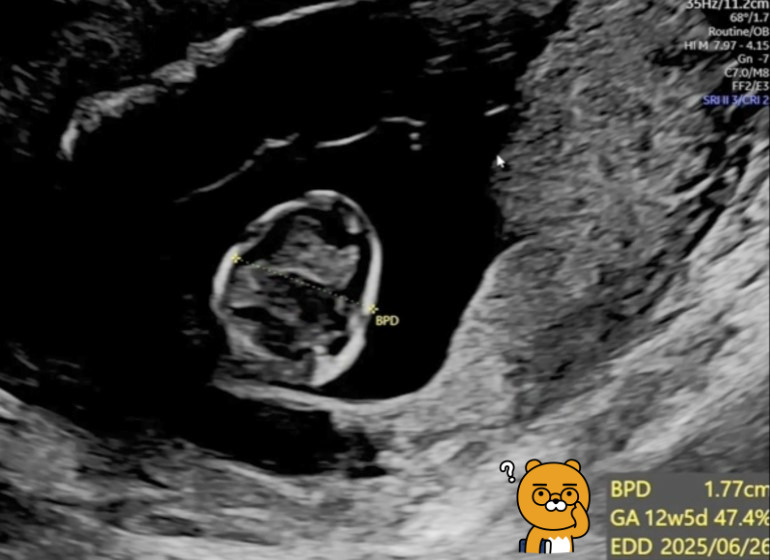

12주 태아 신체 측정.jpg

[왼쪽은 태아 머리 크기와 임신 주수, 오른쪽은 심박수]

♬ BPD(Bioparental Diameter)는 태아 머리 옆통수의 길이를 말하는데, '팡팡이'의 초음파 영상을 보니 1.77cm로 나옵니다. 12주 차가 1.7cm 정도라고 하니 정상이네요.

♬ GA(Gestational Age)와 EDD(Expected Date of Delivery)는 임신 주수와 분만 예정일을 나타내는 것이라고 합니다. 이에 따르면 현재는 임신 12주 5일이고, 분만 예정일은 25년 6월 26일이네요.